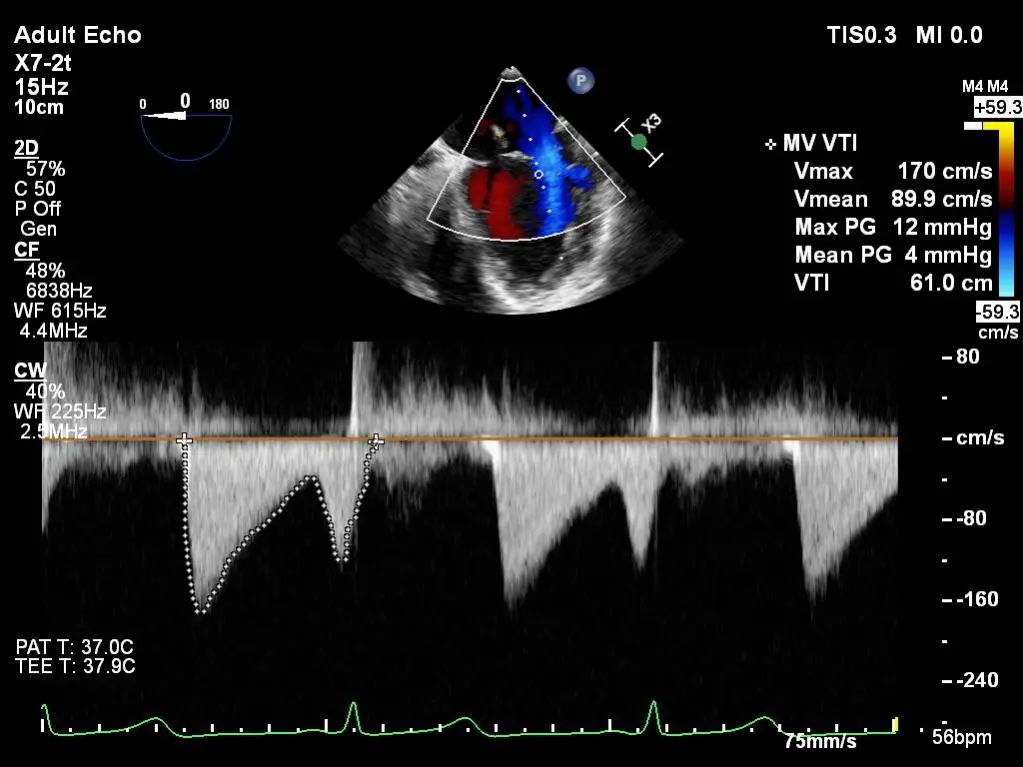

术后肺静脉频谱

二尖瓣瓣口面积及平均跨瓣压差评估(4mmHg)

平均跨瓣压差:5mmHg

二尖瓣瓣口面积及平均跨瓣压差评估(5mmHg)